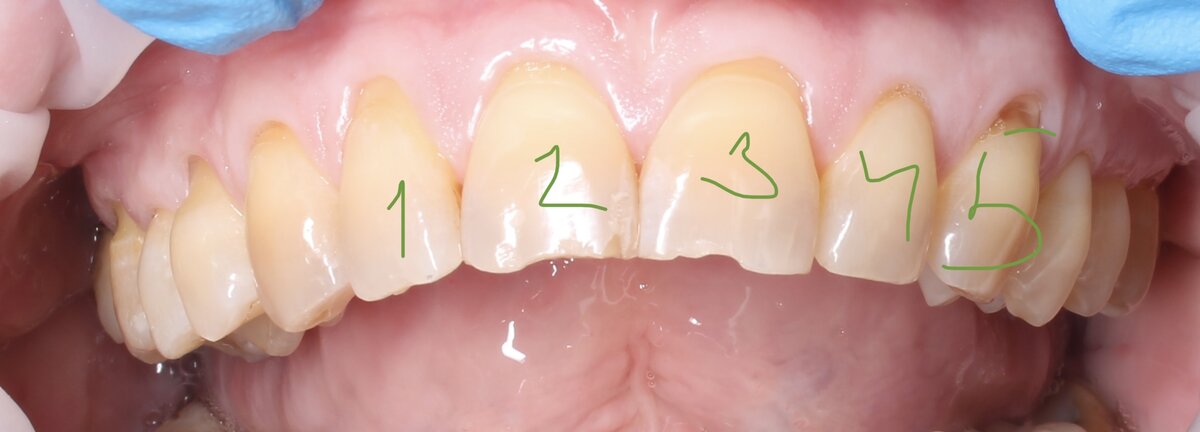

Невооруженным глазом видны рецесси десны (оголение корней).

Пациентка планирует установку виниров на верхние фронтальные 5 зубов. С ортопедом они приходят ко мне и просят подсобить в этом хорошем деле.

То, что хотели закрыть ортопед с пациенткой.